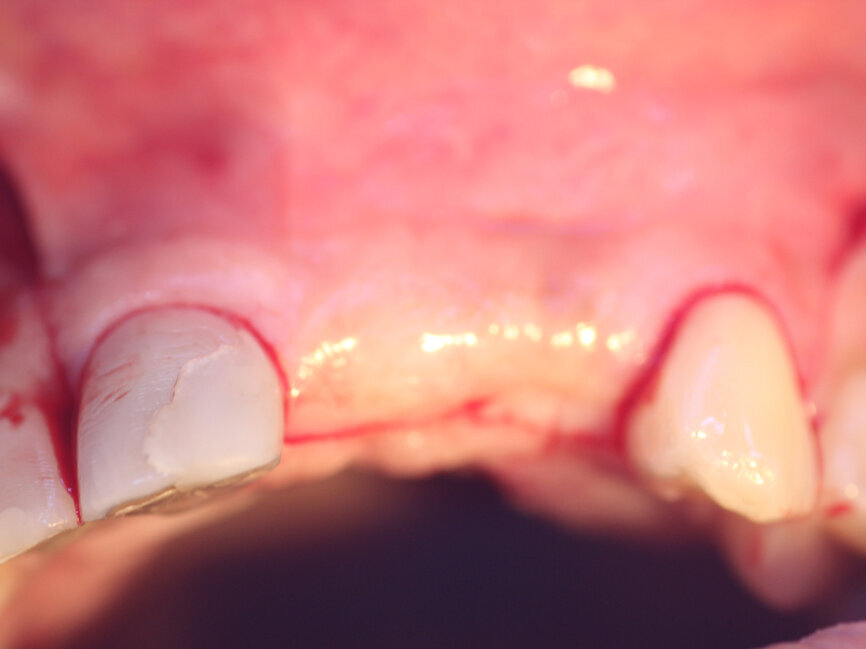

A 52-year-old male patient presented missing the left central and lateral maxillary incisors with a desire to have implants to replace the missing teeth and a fixed prosthetic approach. The patient indicated that the teeth had been extracted eight years before, and clinical examination noted a deficient facial aspect of the ridge at the extraction sites and healthy soft tissue (Fig. 1). A cone-beam CT (CBCT) was taken and evaluated. Cross-sectional views of the edentulous space confirmed inadequate width of the ridge in the facial-palatal dimension to house implants at the adjacent sites (Fig. 2). The patient was informed of the clinical findings and a discussion on augmenting the site with an osseous graft would be necessary for implant placement. As insufficient bone would not permit simultaneous implant placement at the time of grafting, the patient was informed that a healing period of four to six months would be needed between graft placement before implants could be placed. This would then be followed by a four- to six-month period to allow the implants to osseointegrate before any restoration could be placed on the implants. The patient agreed to treatment and was appointed.

Fig. 1: Deficient facial aspect to the anterior maxilla resulting from resorption following tooth extraction. (Photos provided by Dr. Arun K. Garg; Dr. Gregori M. Kurtzman; Dr. Renato Rossi Jr.; and Dr. Maria del Pilar Rios)